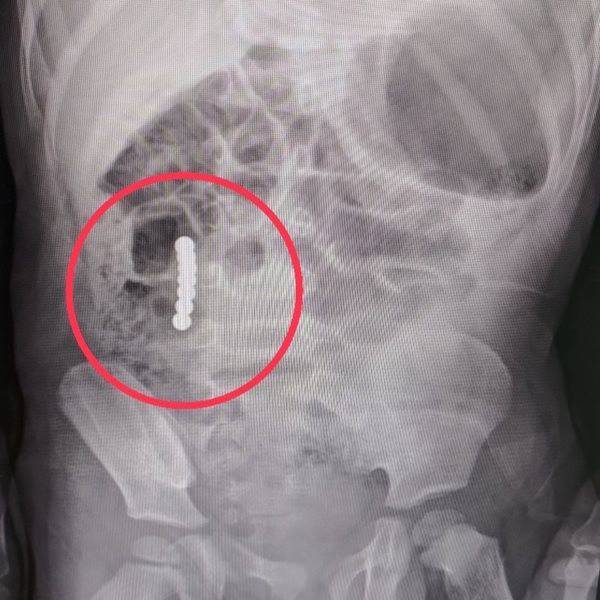

磁力棒誤吞的主要風險在於小型強力磁鐵被兒童吞入後,磁鐵可能在腸道內互相吸附,夾住腸壁,導致嚴重的腸穿孔、腸壞死等腸胃道損傷,甚至危及生命。這種情況尤其發生在吞入兩顆以上磁力球或磁性零件時,磁鐵會隔著腸壁互相吸引,造成腸道被夾住,難以自然排出。

- 腸穿孔:腸壁被磁鐵夾住後穿孔,導致腹膜炎等嚴重感染。

- 腸壞死:血液循環受阻,腸組織壞死,可能需要手術切除壞死部分。